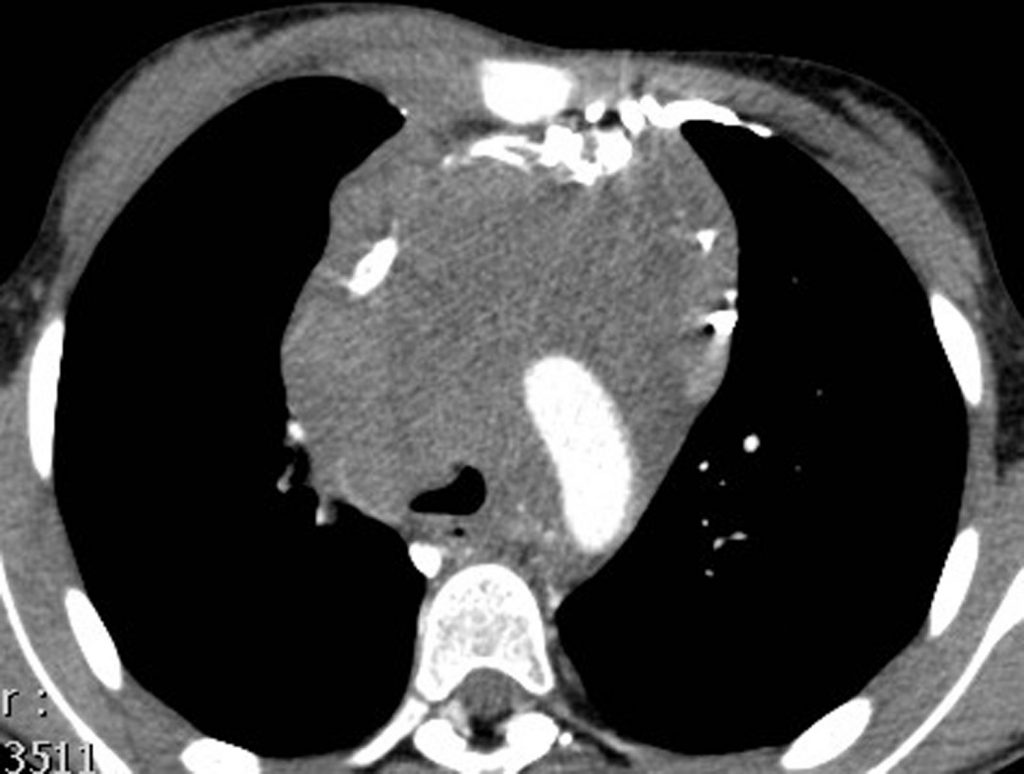

La TDM thoraco-abdomino-pelvienne est systématiquement effectuée pour rechercher des arguments diagnostiques, pour déterminer le site de biopsie et pour évaluer l’extension initiale du lymphome. La TDM thoraco-abdomino-pelvienne permettra la mesure des lésions tumorales cibles qui servira de référence initiale pour l’évaluation de la réponse au traitement ; elle est indispensable pour la détermination des champs de radiothérapie dans les formes localisées de Hodgkin (figure 94.2).

Fig. 94.2. Tomodensitométrie thoracique ; lymphome de Hodgkin.

Masse du médiastin antérieur et moyen refoulant la veine cave inférieure en avant et entraînant une compression de la face antérieure de la trachée.

Source : CERF, CNEBMN, 2022.